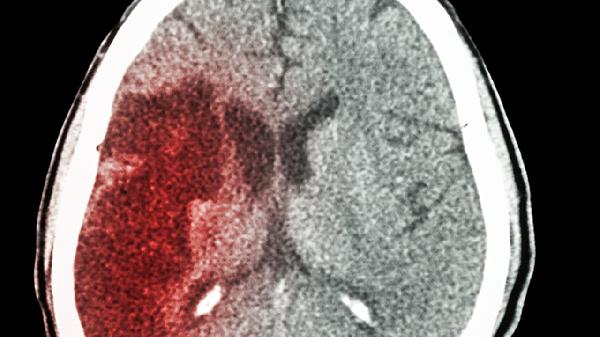

术后颅内出血多发生在手术区域,与血管损伤或凝血功能异常有关,少量出血可自行吸收,大量出血需手术清除。癫痫发作可能与手术刺激皮层或术后瘢痕形成相关,需长期服用抗癫痫药物控制。硬膜下血肿常见于过度引流导致脑组织塌陷,使桥静脉撕裂出血,少量血肿可保守治疗,大量血肿需钻孔引流。部分患者可能出现分流管移位、断裂等机械故障,或对分流材料产生过敏反应。